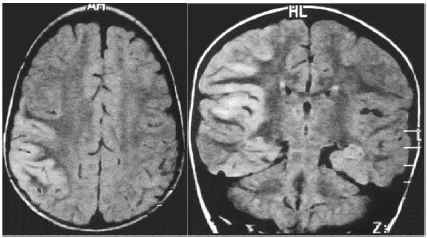

On the other hand, the idea that a patient's own antibodies attack their brain after a virus infection is already established in a type of encephalitis (brain inflammation) that affects adults after a viral infection such as herpes. It can cause severe psychosis which, again, can manifest as hallucinations and self-harm.

Belinda Lennox, a professor of psychiatry at the University of Oxford, has spent more than a decade pioneering the treatment of post-viral encephalitis and, in particular, a form called anti-NMDA receptor encephalitis, an autoimmune disease identified in 2007. .

This type of sudden-onset encephalitis is caused by people's own immune system attacking message-receiving cells in their brains called NMDA receptors, Professor Lennox told Good Health. "These receptors regulate fundamental brain functions," he explains.

"It appears that patients' immune systems are mistakenly prompted to attack these NMDA receptors when they respond to certain viral infections such as herpes simplex, which can look similar to the NMDA receptor."